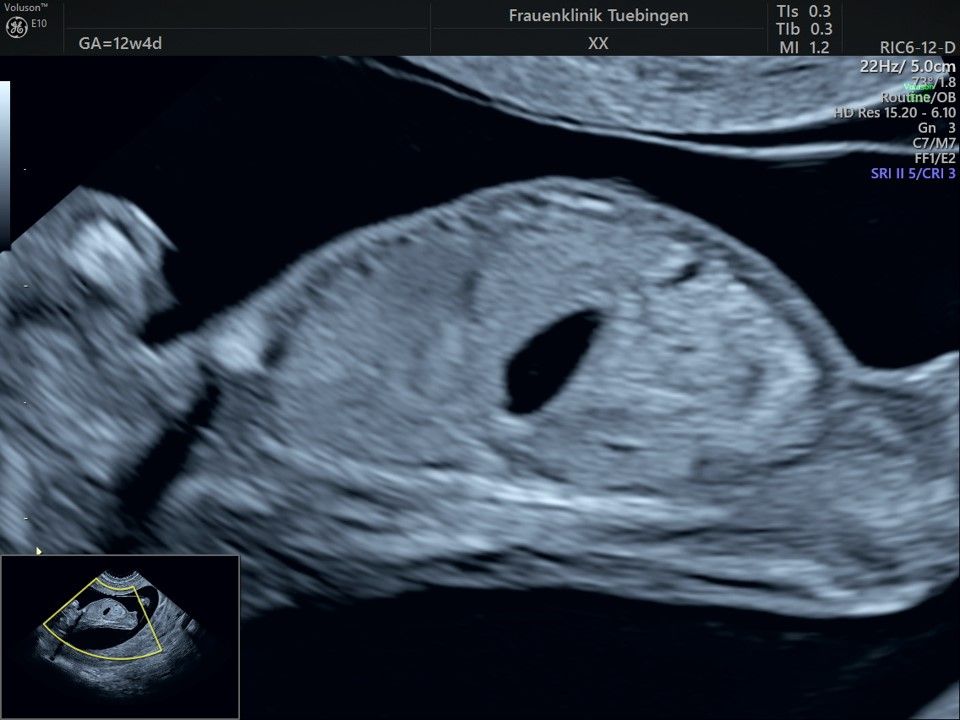

Im Rahmen des Ersttrimester-Screenings untersuchen wir die Organe des Feten mittels Ultraschall. Dabei machen wir auch gerne ein Bild für Sie.

Obwohl der Fet zu diesem Zeitpunkt erst zwischen 5 und 8cm groß ist, lassen sich bereits etwa die Hälfte aller schwerwiegenden Fehlbildungen erkennen bzw. ausschließen. Sollten wir eine Auffälligkeit sehen, werden wir mit Ihnen den Befund und das weitere Vorgehen ausführlich besprechen.

Das Ergebnis der Ultraschalluntersuchung ist wegweisend. Dabei wird der Fet vermessen, die Organe werden untersucht und die sonographischen Marker zur Risikoberechnung für Chromosomenstörungen werden beurteilt. Das sind: die Nackentransparenzdicke, Nasenbein sowie der Blutfluss in der rechten Herzhälfte und im Ductus venosus, einem Gefäß in der Leber des Feten.